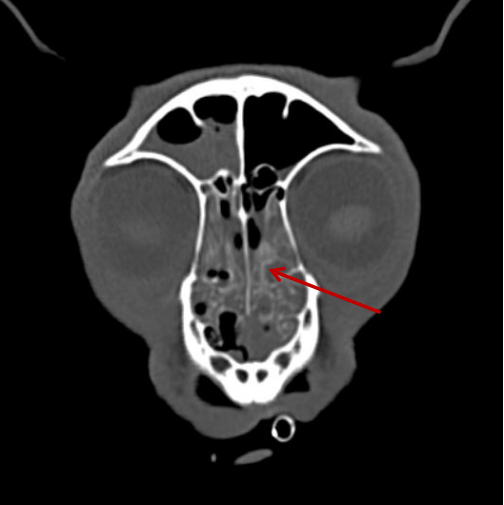

▲小白兔,白又白,兩只耳朵豎起來~這個小家伙也不幸中招,得了肝癌。

▲相比之下,這只狗狗的鼻竇炎可算是小毛病了。